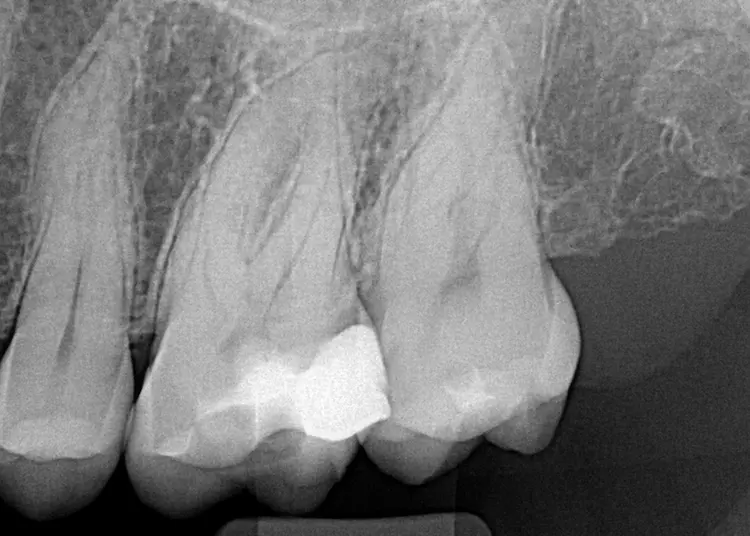

Die Patientin stellte sich mit gelegentlichen Beschwerden in regio 26 vor. Alio loco erfolgte bereits die Erneuerung der Kompositfüllung, wodurch sich die Symptomatik aber nicht verbesserte. Der Zahn reagierte minimal verstärkt auf thermische Reize. Eine Aufbissempfindlichkeit bestand nicht.

Da die zweidimensionale Diagnostik aufgrund der Länge der Wurzeln erschwert war und sich zudem eine komplexe Anatomie vermuten ließ (Abb. 1), wurde zur erweiterten Diagnostik und zur Behandlungsplanung ein kleinvolumiges DVT angefertigt (Orthophos SL, Dentsply Sirona, Volumen Ø 5 x 5 cm, Auflösung 80 μm). In der DVT-Aufnahme zeigte sich eine apikale Osteolyse an der palatinalen Wurzelspitze mit reaktiver Schwellung der angrenzenden basalen Kieferhöhlenschleimhaut (Abb. 2). Der periapikale Knochen an den vestibulären Wurzeln stellte sich unauffällig dar.